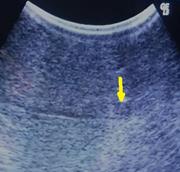

Postcoital hemoperitoneum caused by ruptured corpus luteal cyst: a hidden etiology

Mohamed Mohamed and others

Journal of Surgical Case Reports, Volume 2015, Issue 10, October 2015, rjv120, https://doi.org/10.1093/jscr/rjv120